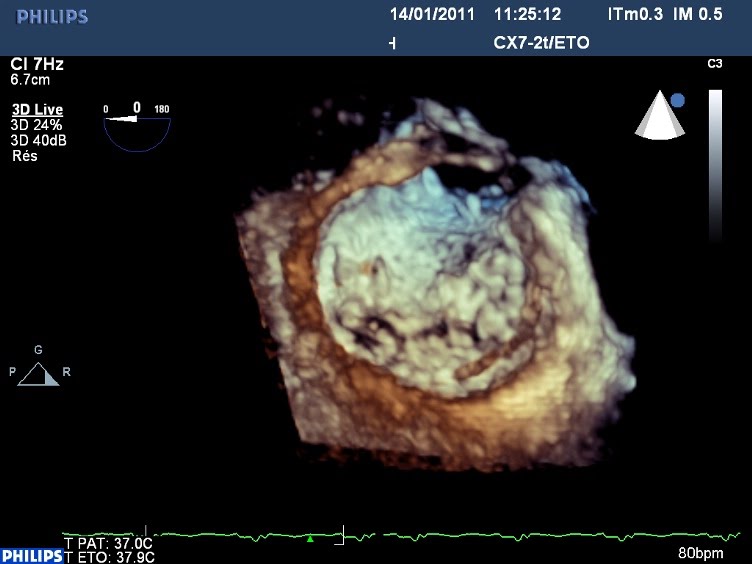

Anneau mitral modélisé en ETO 3d :

Restriction bi-valvulaire : face ventriculaire de la mitrale :

On aperçoit sur la grande valve en haut à gauche (commissure postérieure) et à droite (commissure antérieure) la restriction (signe de « la mouette ») sur la grande valve mitrale: